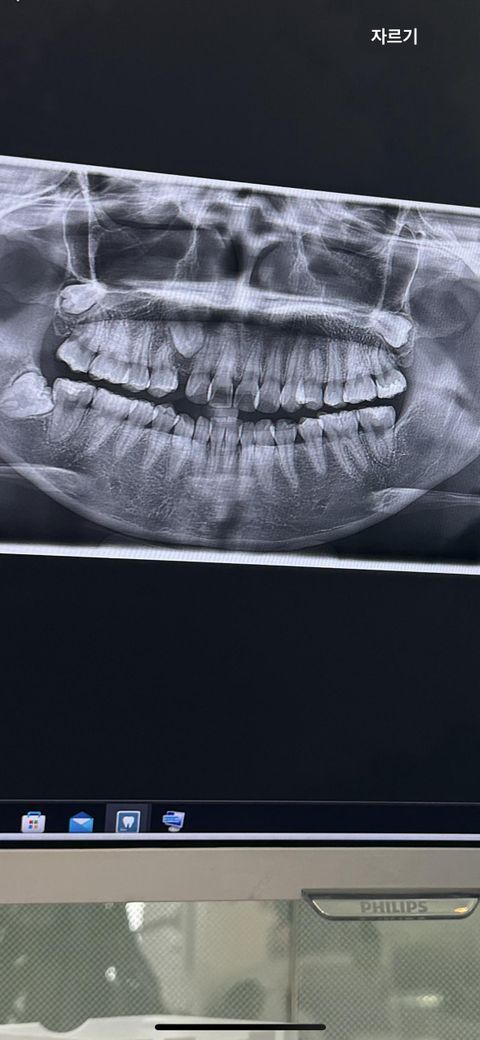

매복송곳니 발치해도 될까요????

현재 나이는 25살이고

송곳니 유치가 고등학교 1학년때 빠졌습니다

그 빠진 틈이 새끼손가락 크기정도 되었는데

몇달 전부터 문득 궁금하여 넣어보니 틈이 줄어들고 있더라구요

그와 동시의 앞니+앞니 옆에 있는 이빨들이 빈틈쪽으로 쏠리는 것도 인지하였습니다.

그래서 교정을 하러 치과를 방문했는데

소구치를 빼고 인견을 하자 그치만 인견을 시도해도 안 내려올 가능성이 있다. 발치를 하는 선택지도 있다 하셨습니다.

송곳니의 경우 발치를 하면 안된다고 들었는데 사실 왼쪽 송곳니도 덧니로 나 있어서 평생 송곳니가 없이 살았어서 뺀다고 해도 기능적으로 문제가 있을까싶어 고민끝에 송곳니발치를 하겠다고 하고 교정기를 윗니만 붙이고 왔습니다. 그치만 이게 맞는 선택인건지 궁금합니다…….

• 1번 째 사진

교정을 하실꺼면 매복 송곳니를 견인해서 사용할지 그게 아니라면 매복 견치를 발치를 하셔야될것같습니다.

현재 매복되어있는 치아의 견인 여부에 따라서 치료 계획이 달라질 것으로 보이며 현재로선 견인을 시도해보는 것 까지는 맞는 듯 합니다.

25세이니 담당 치과선생님이 송곳니가 안내려 올 가능성이 높다고 판단하였다면 그 판단에 따라야 합니다. 제가 보기에도 내려오기 어려울 것으로 보입니다.

견인 시도 먼저 해보고 빼는 것이 어떨까 싶습니다. 안되면 빼고 치열 당기는 교정을 해주면 될 거 같습니다.